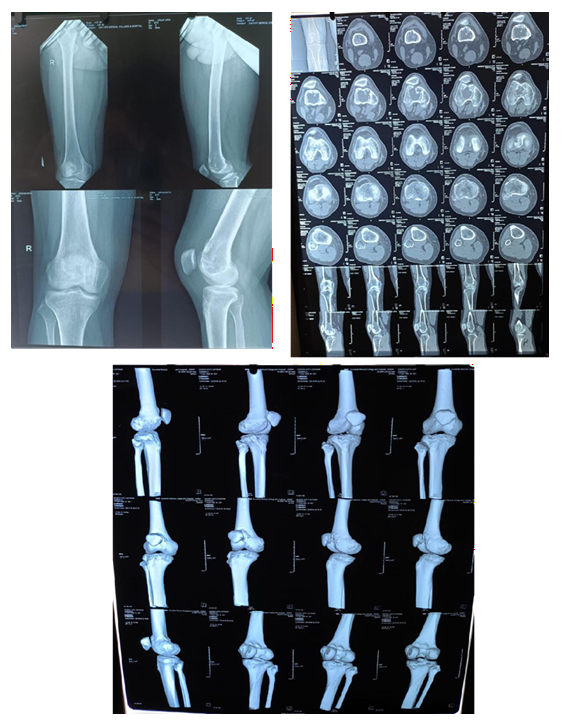

Case 2:

MRI

Pre Denosumab

Post Denosumab

Intraoperative

Post Operative